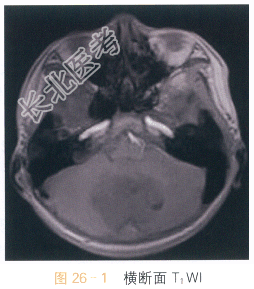

男,9岁,头痛4月余。

读片分析:头颅横断面T₁WI见小脑蚓部巨大软组织肿块影,呈不均质低信号,形态不规则,边界不清;横断面T₂WI可见病灶呈不均质高信号,周围可见瘤周水肿;增强扫描肿瘤部分可见不均质强化。